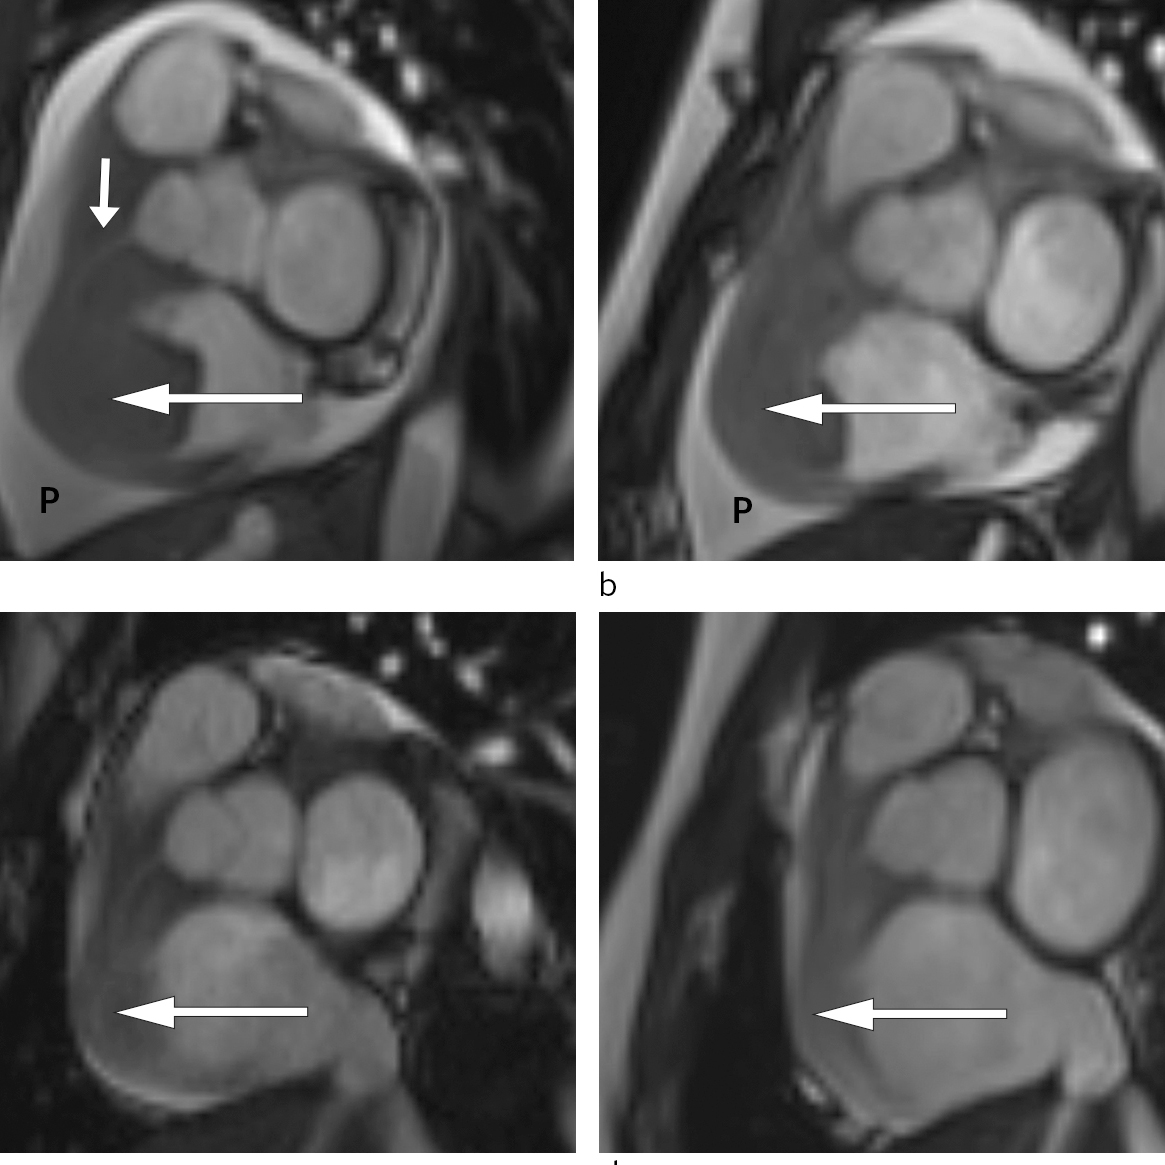

Allereie timar etter at behandlinga tok til merka pasienten avtakande brystsmerter og mindre dyspné. To dagar seinare var det mogleg gjennomføre MR-undersøking av hjartet. Denne bekrefta persisterande tumormassar i høgre atrium og høgre ventrikkel med gjennomvekst av ventrikkelvegg og samanlodding av trikuspidalsegla (fig 3).

Pasienten vart i denne fasen observert i hjarteovervakingsavdelinga. Det vart ikkje observert arytmiar eller andre komplikasjonar til behandlinga. Ho fekk lågdosert fraksjonert heparin som tromboseprofylakse. Repetert MR-undersøking som vart gjort tre dagar etter oppstart med CHOP-regimet, viste betydeleg regress av oppfyllinga i høgre hjartehalvdel og nærast total regress av intrakavitære komponentar. Den atrioventrikulære opninga på høgre side var betydeleg større enn ved den initiale MR-undersøkinga (fig 3).

Pasienten gjennomgjekk ytterlegare blokkurbehandling. Radiologisk evaluering etter andre behandling viste nærast total regress av tumormanifestasjonat i abdomen (fig 3). Ein har heldt fram med R-CHOP-regimet, som har helde sjukdomen i remisjon sidan.

Kortikosteroidbehandling vart starta før endeleg histologisvar låg føre. Kortikosteroid har ein generell antiinflammatorisk effekt, i tillegg til ein direkte cytotoksisk effekt på lymfoide celler. Då histologisvaret låg føre, kunne ein begynne med meir målretta behandling av kreftsjukdomen. I dette tilfellet var det viktig å følgje med på behandlingsresponsen både for primærtumoren i abdomen og oppfyllinga i hjartet fordi ein kausal samanheng ikkje var sikker. Ved respons (fig 3) var det naturleg å tenkje seg ein slik samanheng.